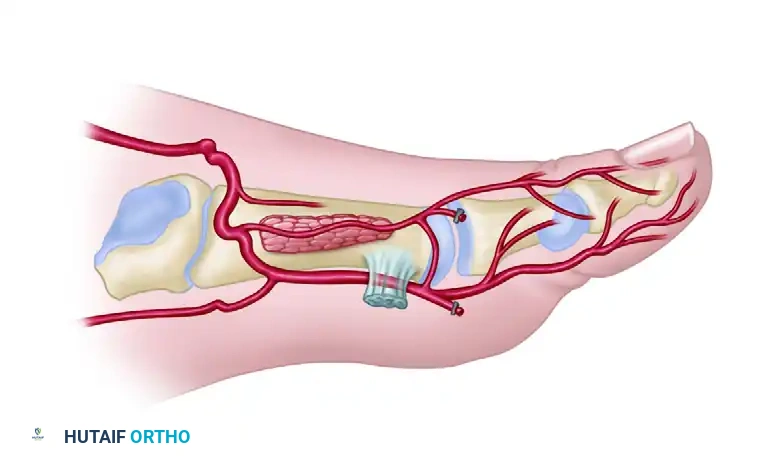

A masterful grasp of the dorsal foot vascular architecture is the foundation of a successful dorsalis pedis free flap. The primary arterial supply is the dorsalis pedis artery (DPA), a direct continuation of the anterior tibial artery as it passes deep to the extensor retinaculum.

As the DPA courses distally over the dorsal aspect of the tarsal bones, it gives off the lateral and medial tarsal arteries, followed by the arcuate artery.

Distal to the arcuate artery, the DPA bifurcates into two terminal branches:

1. First Dorsal Metatarsal Artery (FDMA): Courses distally within the first intermetatarsal space to supply the dorsal skin of the great and second toes.

2. Deep Plantar (Communicating) Artery: Plunges plantarly between the two heads of the first dorsal interosseous muscle to anastomose with the lateral plantar artery, completing the plantar arch.

- Venous: The flap is drained by two systems: the deep venae comitantes accompanying the DPA, and the superficial venous system draining into the greater saphenous vein. Both should be harvested to ensure robust venous outflow.